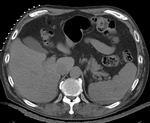

Intra-subject liver & kidney CT / MRI: preop-scan to intra-op scan

this is the fixed reference image. All images are aligned into this space lleft this is the moving image. The transform is calculated by matching this to the reference image

fixed image/target moving image

• reference/fixed : intra-operative CT, 1x1x5 mm voxel size, 512x512x41, axial

• moving 1: pre-operative MRI, 0.8x0.8x2.5 mm voxel size, 512x512x96, axial

• moving 2: pre-operative contrast CT, 0.9x0.9x5 mm voxel size, 512x512x42, axial